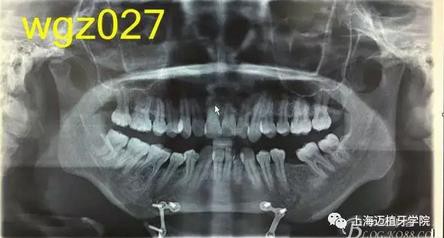

圖1

曲面斷層片:28顆恒牙,LL6缺失,牙槽骨均位于釉牙骨質(zhì)界以下,LR6、LL7近中牙槽骨角型吸收,頦部可見成型術(shù)鈦合板。左側(cè)升支較右側(cè)粗。

關(guān)節(jié)片:左右髁突不對稱,髁狀間隙右側(cè)明顯較左側(cè)寬,右側(cè)間隙清楚,大小勻稱 ,左側(cè)欠佳。